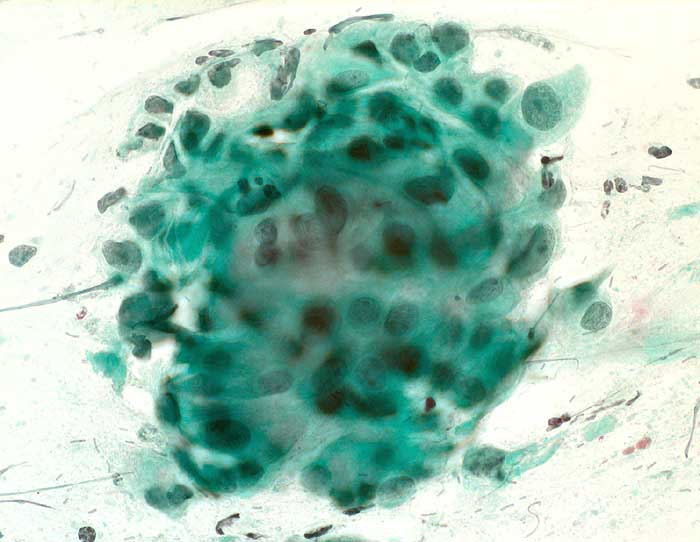

PathoPic – image database / PathoPic ID 6232 - reaktiv veränderte Zylinderepithelien

reaktiv veränderte Zylinderepithelien

Portioabstrich: mehrere sehr grosse Kerne mit Zylinderzellen und Nacktkernen. Chromatin normal, fein und regelmässig verteilt. Keine vergrösserten Nukleolen.

Zytologische Diagnose: Unverdächtig. Reaktive Zellveränderungen mit vergrösserten Kernen, wie unter Gestagen-Behandlung.